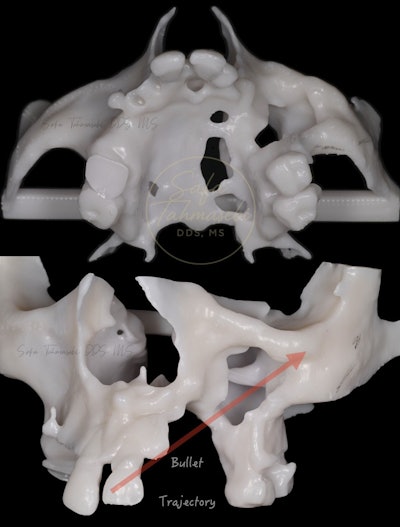

Figure 3: A forensic bone model demonstrates the bullet's trajectory and resulting damage to the man's mouth.

Figure 9: An anatomical model demonstrates how Dr. Tahmasebi reconstructed John Doe's maxilla.